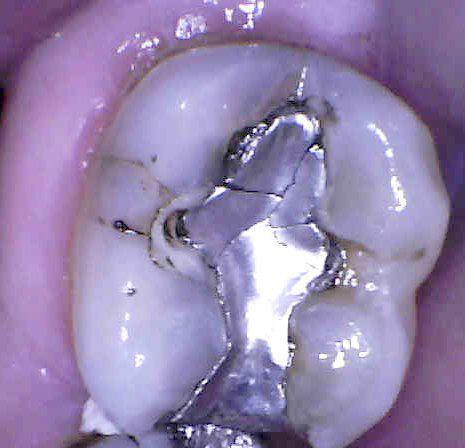

silver filling before | charlotte ncwhite fillings | charlotte nc

Safe Mercury Amalgam Removal Technique (SMART)

We are certified by the International Academy of Oral Medicine and Toxicology to provide safe mercury amalgam removal. We now know that mercury particles and vapors are released into the air when old silver fillings are removed, which can be detrimental to your health, dental personnel health, and the environment.  Our goal is to provide you with the highest quality dental work in a safe environment, so we added new equipment and trained on specific protocols to ensure the greatest level of protection possible! safe mercury amalgam removal technique charlotte

• Rubber dental dam placed on tooth for isolation- while removing the old mercury amalgam, we use high speed suction to catch the debris and water, as well as a rubber dam to isolate the tooth from the rest of the mouth

Many people choose to remove metal restorations from their mouths not just for cosmetic reasons, but because they have sensitivities to non-precious metals such as nickel. Sometimes the gum tissue around a metal or porcelain fused to metal crown is very red, inflamed, and bleeds easily- all signs of a metal allergy.